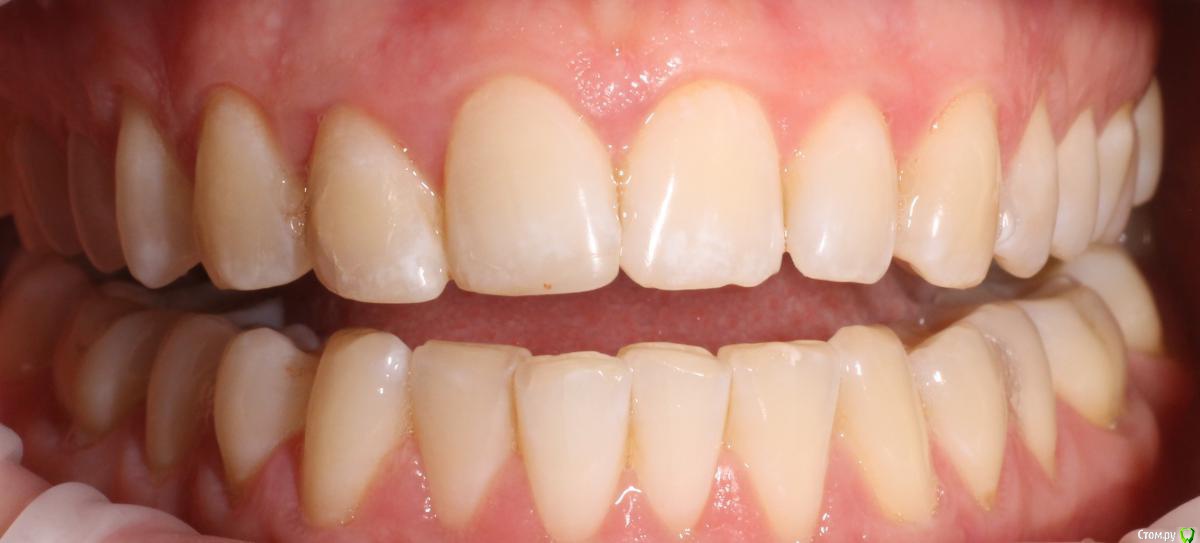

MenshikovDV Опубликовано 2 апреля, 2015 Поделиться Опубликовано 2 апреля, 2015 (изменено) Зуб 1.2 отлом коронковой части зуба, на период ожидания приема у хирурга и ортопеда (2 дня) приклеен к соседям. Вся процедура в одно посещение. Где-то часа два. Я ортопед, хирургия не моя, фото мои Изменено 2 апреля, 2015 пользователем MenshikovDV 19 Ссылка на комментарий